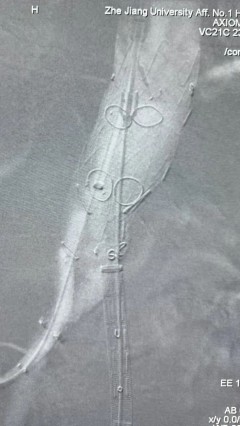

6. 解除束径,打开近端后释放,经肱动脉长鞘超选支架外分支,并进一步超选右侧肾动脉,交换加硬导丝,送入覆膜支架6*50mm和7*60mm各一枚,并予以球囊后扩张,手推造影显影良好。

7. 经长鞘重新选入左侧外分支,并超选进左肾动脉,沿导丝送入外周血管覆膜支架7*60mm一枚,并予以球囊后扩张,手推造影显影良好。

8. 从右侧股动脉入路送入腹主支架AB-24-12-110-S,近端重叠胸腹主动脉支架远端,调整好支架位置后释放。